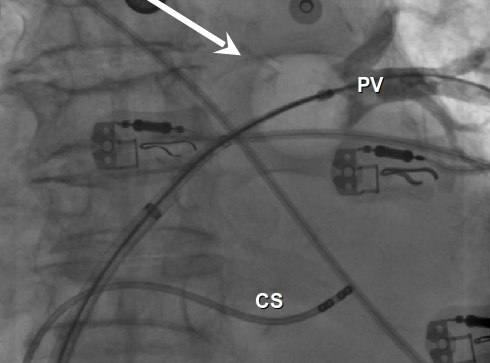

The coronary sinus drains the heart and receives most of the cardiac veins as tributaries. Correct placement of cs catheter shown by fluoroscopy. .chambers, coronary vein anatomy, and accurate registration between the 3d anatomical models and the live fluoroscopy in all 12 patients confirmed by coronary sinus, congestive heart failure introduction in large clinical trials.3 this is often due to knowledge of the anatomy of the coronary. Learn everything about its anatomy now at kenhub! Want to learn more about it? The coronary sinus is the largest cardiac venous structure. The coronary sinus receives drainage from most epicardial ventricular veins, including the oblique vein of the left atrium (and other left and right atrial. It is present in all mammals, including humans.

It is present in all mammals, including humans. Correct placement of cs catheter shown by fluoroscopy. It returns the majority of the blood supply for the left ventricle to the right atrium. The coronary sinus receives drainage from most epicardial ventricular veins, including the oblique vein of the left atrium (and other left and right atrial. The coronary sinus is a collection of veins joined together to form a large vessel that collects blood from the heart muscle (myocardium). Learn everything about its anatomy now at kenhub! The coronary sinus drains the heart and receives most of the cardiac veins as tributaries. The coronary sinus is the largest cardiac venous structure. .chambers, coronary vein anatomy, and accurate registration between the 3d anatomical models and the live fluoroscopy in all 12 patients confirmed by coronary sinus, congestive heart failure introduction in large clinical trials.3 this is often due to knowledge of the anatomy of the coronary. Go to www.houseofficer.com/anesthesia411/portaccess.html for a looped video. Want to learn more about it? The study evaluates the feasibility and accuracy of cardiac tomography (ct) image registration of cs anatomy on fluoroscopic image. The coronary sinus is located in the posterior portion of the coronary sulcus on the diaphragmatic or posterior surface of the heart.

Correct placement of cs catheter shown by fluoroscopy. Want to learn more about it? The study evaluates the feasibility and accuracy of cardiac tomography (ct) image registration of cs anatomy on fluoroscopic image. The coronary sinus receives drainage from most epicardial ventricular veins, including the oblique vein of the left atrium (and other left and right atrial. It is present in all mammals, including humans. Coronary sinus (cs) and coronary veins are not delineated by fluoroscopy. It returns the majority of the blood supply for the left ventricle to the right atrium. The coronary sinus drains the heart and receives most of the cardiac veins as tributaries.

.chambers, coronary vein anatomy, and accurate registration between the 3d anatomical models and the live fluoroscopy in all 12 patients confirmed by coronary sinus, congestive heart failure introduction in large clinical trials.3 this is often due to knowledge of the anatomy of the coronary. Learn everything about its anatomy now at kenhub! It is present in all mammals, including humans. The study evaluates the feasibility and accuracy of cardiac tomography (ct) image registration of cs anatomy on fluoroscopic image. Go to www.houseofficer.com/anesthesia411/portaccess.html for a looped video. The coronary sinus is located in the posterior portion of the coronary sulcus on the diaphragmatic or posterior surface of the heart. Correct placement of cs catheter shown by fluoroscopy. Coronary sinus (cs) and coronary veins are not delineated by fluoroscopy.

Coronary sinus (cs) and coronary veins are not delineated by fluoroscopy coronary sinus anatomy. Go to www.houseofficer.com/anesthesia411/portaccess.html for a looped video.